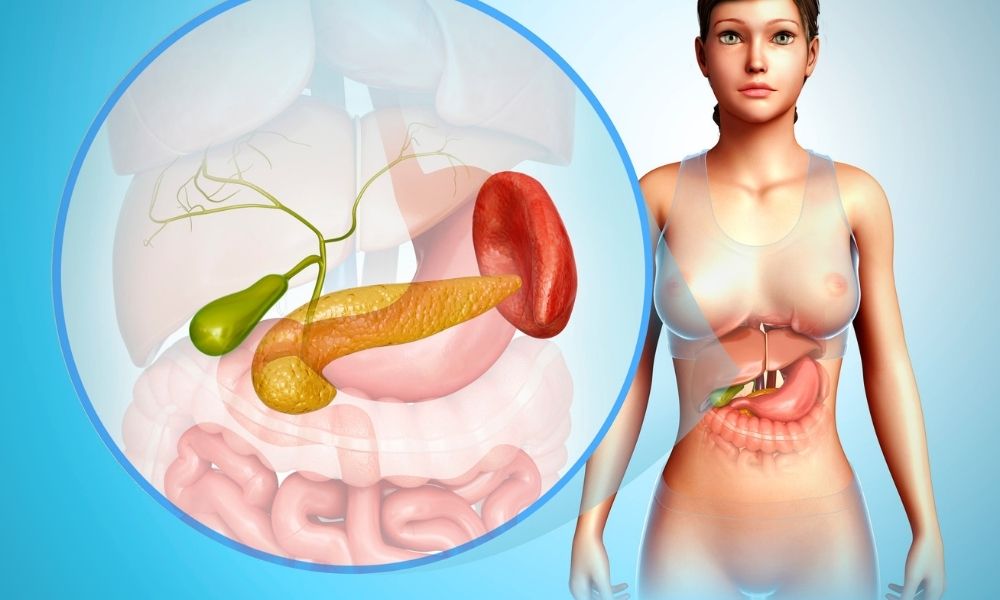

GGT (Gama Glutamil Transferaz) vücudumuzda bulunan bir enzimdir ve karaciğer, safra kanalları ve pankreas gibi organlarda üretilir. GGT testi, kanınızdaki...

Pankreas kanseri, vücudun sindirim sistemini kontrol eden pankreas hücrelerinde anormal bir büyüme olarak tanımlanır. Bu tür kanserin belirtileri genellikle erken...